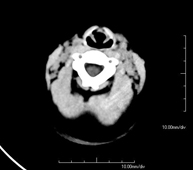

- TC Cráneo

Prueba radiológica que consiste en obtener imágenes del cráneo de alta definición anatómica (tronco cerebral, cerebelo, cerebro, calota craneal, etc.), mediante el empleo de un equipo de TC (Tomografía Computarizada).Indicaciones: traumatismos, cefalea, trastornos de la memoria, pérdida de fuerza súbita en una extremidad o mitad del cuerpo.

Prueba radiológica que consiste en obtener imágenes del cráneo de alta definición anatómica mediante el empleo de un equipo de TC (Tomografía Computarizada). Indicaciones: cefalea, estudio de tumores, traumatismo craneal.